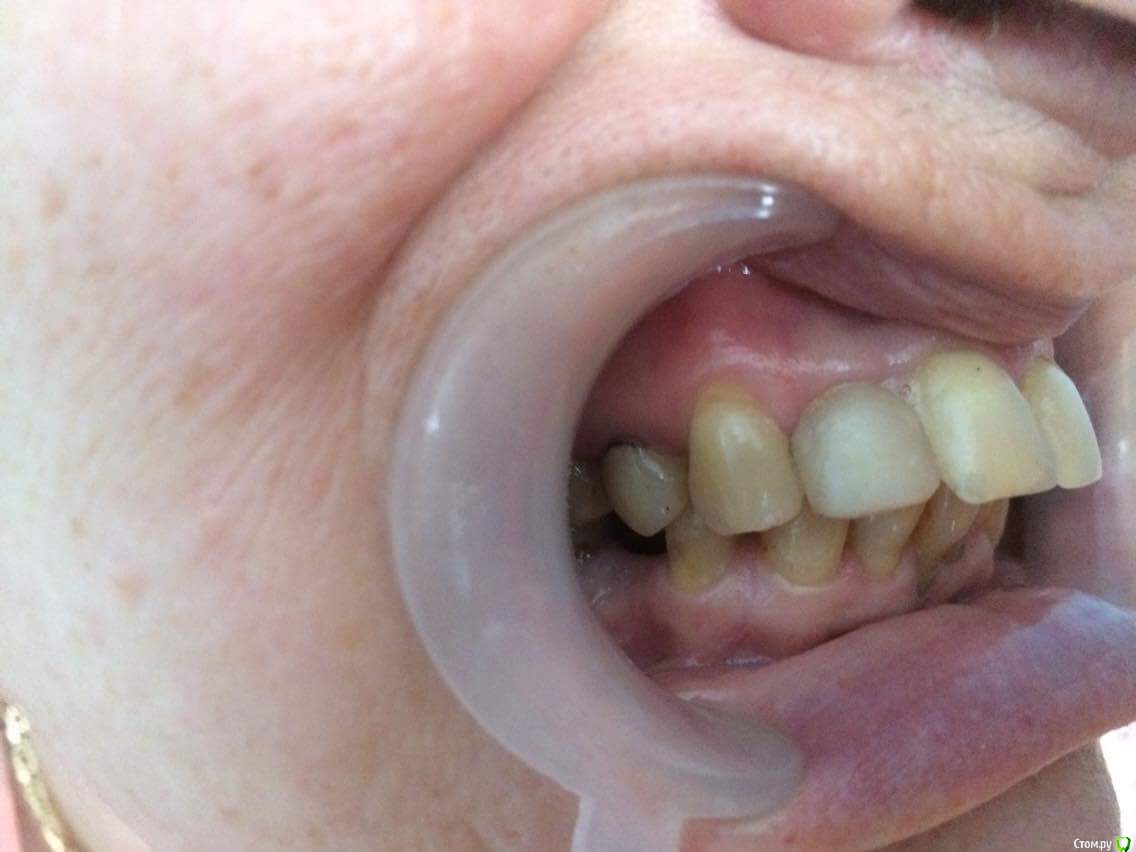

dr.Dre Опубликовано 27 июня, 2017 Поделиться Опубликовано 27 июня, 2017 Добрый день коллеги тему уже создавал но дал мало информации ,пациентка 58 лет .Помогите составить план лечения,имплантацию не потянет .Нужно ли здесь поднимать прикус? Ссылка на комментарий

chervoncevdaniil Опубликовано 27 июня, 2017 Поделиться Опубликовано 27 июня, 2017 (изменено) Док,фотопротокол вам мягко говоря подтянуть надо, боковые вообще не видно.Про имплантацию мы поняли,а остальное?Устраивает ли ее эстетика фронта,или просто хочет чтобы было чем жевать в боковом отделе?Как к съемному протезированию относится,потому что иначе вы 3 сегмент не закроете.Плюс вы же понимаете,что если вы прикус поднимете,то автоматически под коронки/виниры/накладки пойдут все зубы,включая интактный нижний фронт и витальные верх это вы с пациенткой обсудили? Может после этого уже и на имплантацию мотивация появится? Изменено 27 июня, 2017 пользователем chervoncevdaniil Ссылка на комментарий

dr.Dre Опубликовано 27 июня, 2017 Автор Поделиться Опубликовано 27 июня, 2017 Док,фотопротокол вам мягко говоря подтянуть надо, боковые вообще не видно.Про имплантацию мы поняли,а остальное?Устраивает ли ее эстетика фронта,или просто хочет чтобы было чем жевать в боковом отделе?Как к съемному протезированию относится,потому что иначе вы 3 сегмент не закроете.Плюс вы же понимаете,что если вы прикус поднимете,то автоматически под коронки/виниры/накладки пойдут все зубы,включая интактный нижний фронт и витальные верх это вы с пациенткой обсудили? Может после этого уже и на имплантацию мотивация появится?Эстетика не устраивает,пациент хочет все делать полностью ,к сьемному относиться отрицательно.Хочет ровные красивые зубы Ссылка на комментарий

chervoncevdaniil Опубликовано 27 июня, 2017 Поделиться Опубликовано 27 июня, 2017 (изменено) Ну в таком случае я не знаю как вы будете низ боковые сегменты протезировать,но 36 однозначно под удаление,26 и 27 в связи с деформацией плоскости видимо тоже придется,47 и 17 под вопросом и у нее получаются концевые дефекты.Опять же повторюсь,очень плохо видно что в боковом отделе,но настолько прикус вы навряд ли поднимете,чтобы и боковые зубы остались и при этом фронт не получился как у лошади,потому что по размерам резцы и клыки абсолютно нормальные Изменено 27 июня, 2017 пользователем chervoncevdaniil Ссылка на комментарий